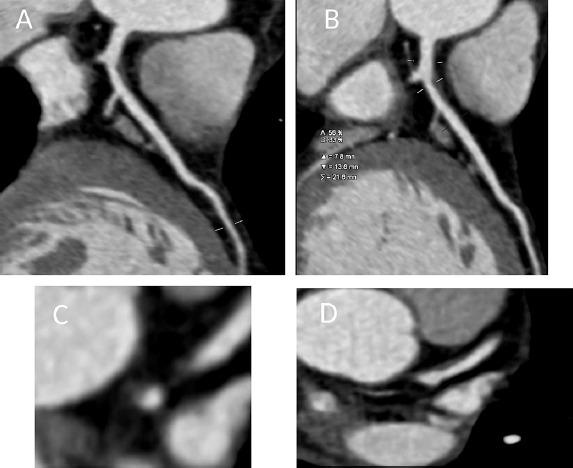

近年来,心脏CT技术的快速发展提高了图像质量,并减少了患者的辐射暴露。此外,大型队列试验的关键见解有助于将心血管疾病风险描述为总体冠状动脉斑块负荷和单个斑块形态外观的函数。CT衍生的血流储备分数的出现有望在一种检查方式中建立解剖学和功能测试。最近发表了关于CT衍生的血流储备分数对下游治疗和临床结果的短期影响的数据。此外,机器学习是一个越来越多地应用于诊断医学的概念。在未来十年中,机器学习将开始融入心脏CT,并可能对这种检查方式的发展产生切实影响。作者对心脏CT的最新进展进行了广泛的文献综述和全面分析。他们回顾了最近的进展如何影响当前的临床护理以及这种成像方式未来可能的发展方向。